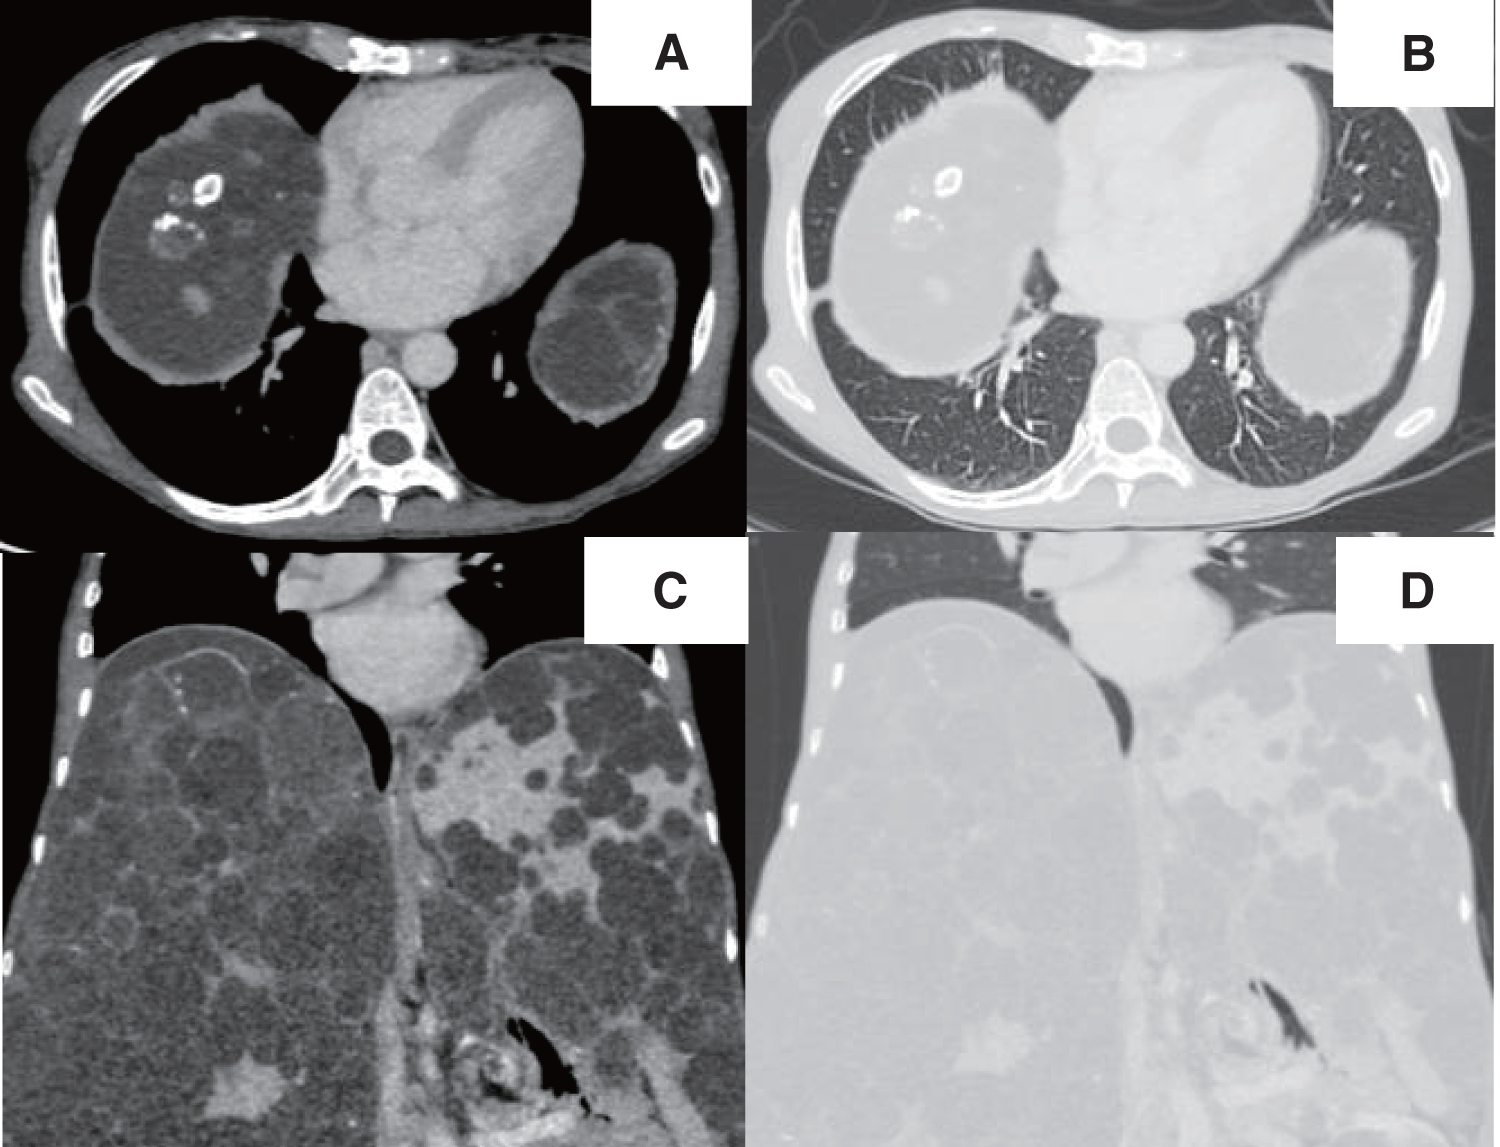

A chest radiograph revealed a round hypertranslucency with air–fluid levels on the right side since POD 1 (Fig. 1B and 1C), and no further evaluation was made at that time. However, because the hypertranslucency persisted, follow-up computed tomography (CT) was performed on POD 18, and revealed an air–fluid level above the diaphragm in the right thoracic cavity (Fig. 3A–3D). The patient was initially considered to have an intrathoracic hematoma, and thoracoscopic evacuation of the hematoma was planned.

The typical appearance of a pneumatocele on CT is a round thin-walled cavitary lesion with air–fluid levels.9,10) In our case, the CT findings were compatible with a pneumatocele (Figs. 3A–3D), but we could not make a correct preoperative diagnosis. This was largely driven by the incorrect assumption that liver surgery would not cause structural changes in the lung parenchyma unless there was direct injury. Additionally, a small hole in the diaphragm could be a source of unusual air retention in the thoracic cavity. Eventually, we considered that a pneumatocele had formed in our patient, triggered by the remarkable alleviation of the distended diaphragm.